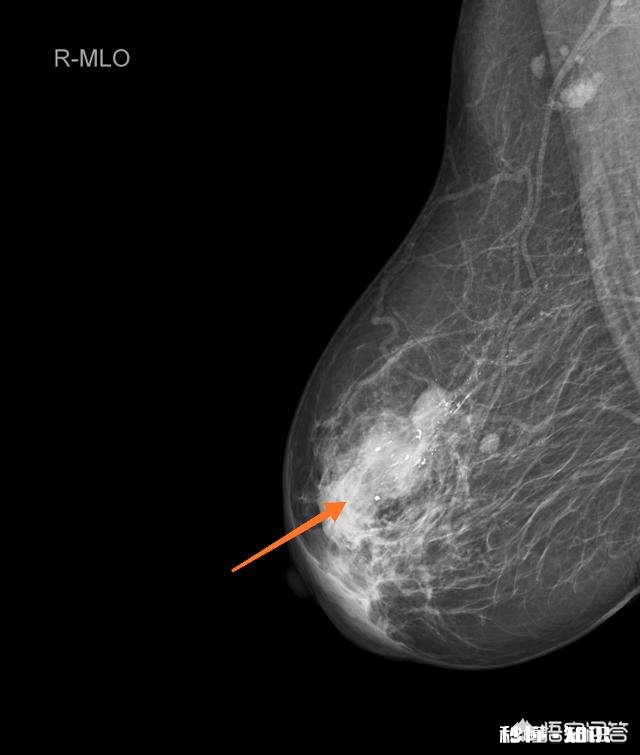

乳腺癌不一定伴有钙化,有钙化不一定是乳腺癌 。下面这个图就是一个典型的乳腺癌钼靶表现,但是并未发现钙化 。

文章插图